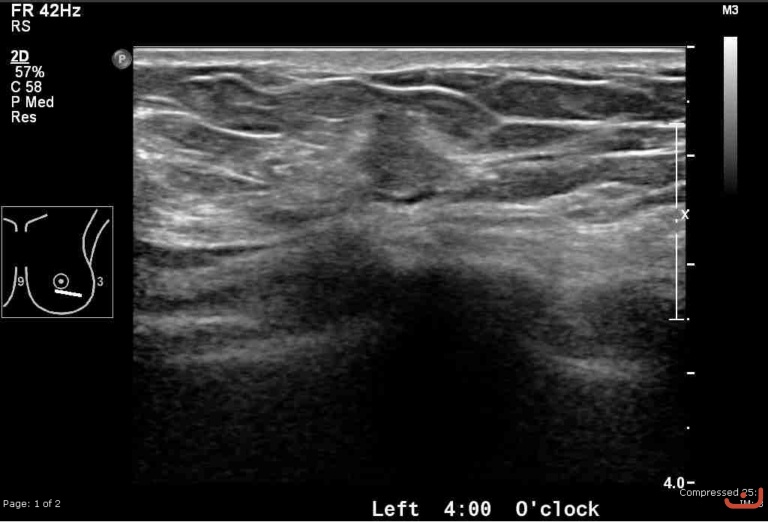

Malignant solid mass

Date

Thursday, 30 April 2015

File size of the original image

167.75 KB (768 x 522 px)